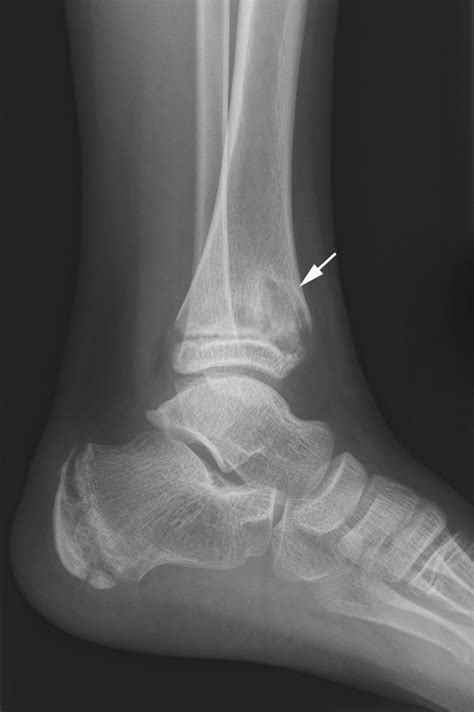

Diagnostic Approach and Imaging

Diagnosing Chronic Multifocal Osteomyelitis is a process of exclusion. Because there is no single laboratory blood test that confirms the diagnosis, physicians rely on a combination of clinical findings, imaging, and, in some cases, a bone biopsy to rule out other more serious conditions like malignancy or bacterial osteomyelitis.

X-rays Useful for evaluating bone damage, though often normal in the early stages.